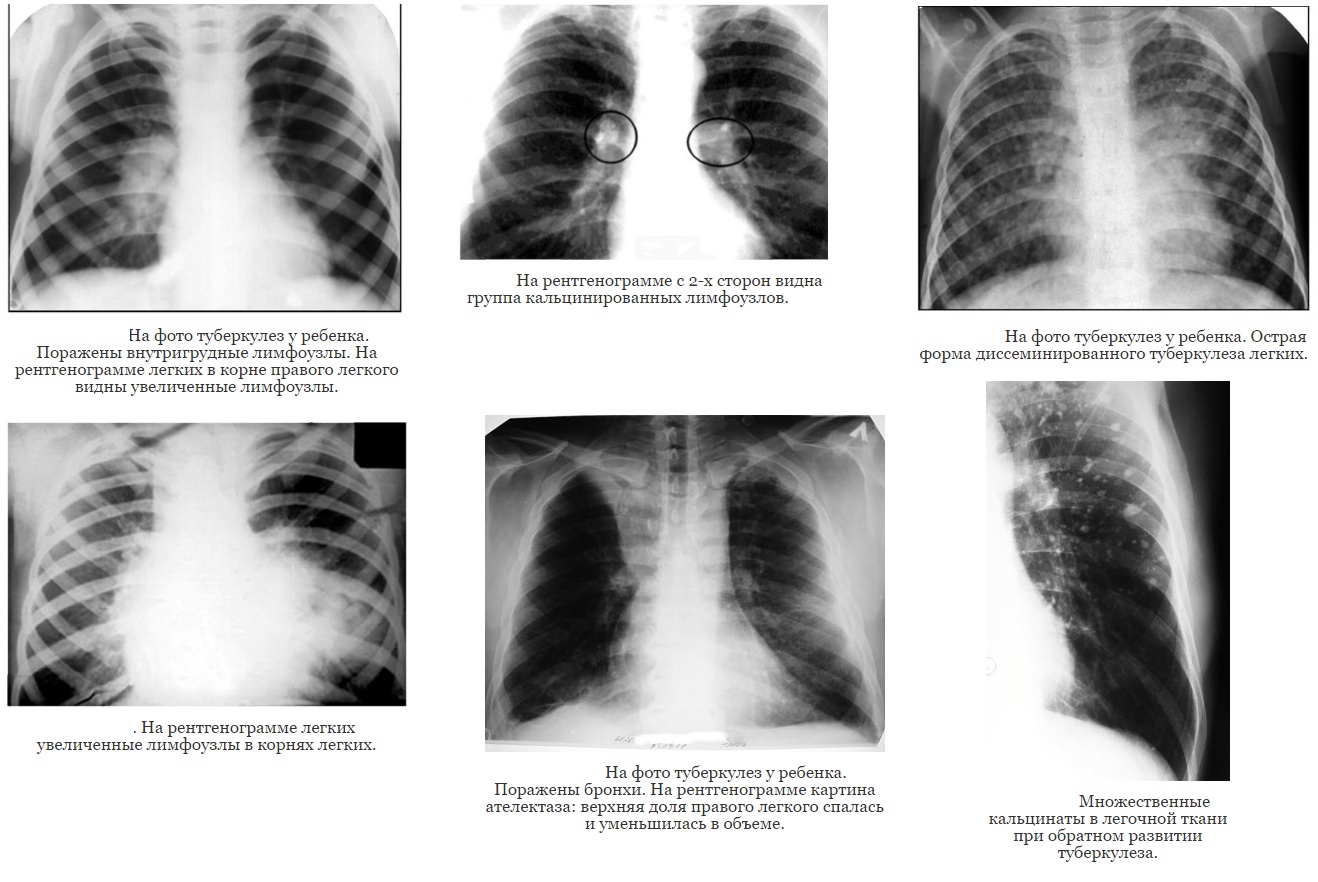

Туберкулез внутригрудных лимфатических узлов.

Такое заболевание встречается у детей наиболее часто. При неосложненном течении инфекцией поражены несколько лимфоузлов, ярко выраженные симптомы отсутствуют. Туберкулезные капсулы кальцинируются, дальнейшее размножение микобактерий не происходит. При осложненной форме инфекция распространяется на соседние лимфоузлы и ткани. Такая форма нередко поражает детей в возрасте моложе 3 лет, имеющих наиболее слабый иммунитет.

Рентген-снимки легочного туберкулеза у детей. Нажмите на фото, для увеличения.